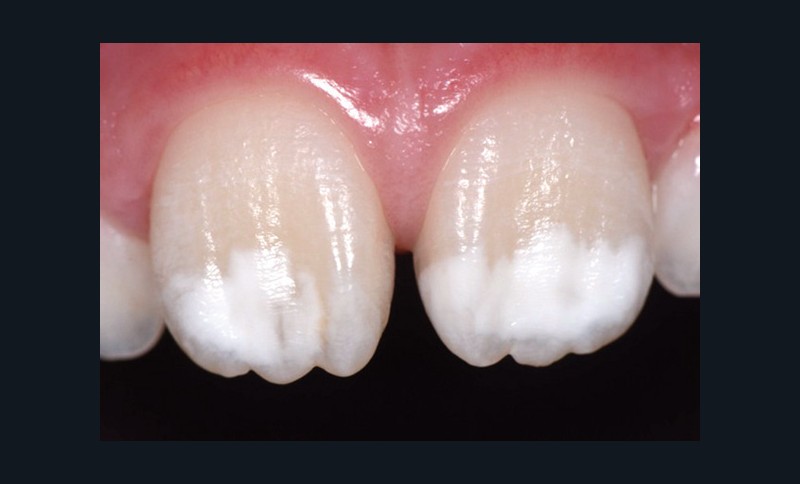

Traitement ultra-conservateur des taches de l’émail : bilan avec 5 ans de recul

Jean-Pierre Attal, Gil Tirlet (Paris)

Les auteurs de cette conférence nous proposent un algorithme pour résoudre le problème des taches blanches de l’émail. Ces techniques sont désormais utilisées avec succès depuis 10 ans. Tout d’abord il convient souvent de réaliser un éclaircissement préalable : celui-ci diminue le contraste entre la tache et le reste de la dent. Ensuite, avant de poser le champ opératoire, il faut choisir la teinte du composite qui sera nécessaire à la fin du traitement. Un sablage/fraisage des taches les plus profondes est alors réalisé, en fonction de la profondeur de la tache. Vient alors l’infiltration ou masquage optique, qui fonctionne sur les taches blanches : on passe une solution d’acide chlorhydrique, puis une solution d’hypochlorite de sodium, et si la tache est devenue blanche alors il est possible de passer à l’infiltration par la résine. Enfin, s’il subsiste une concavité visible, un composite viendra la combler. Le polissage clôt alors le protocole(fig. 11 et 12).